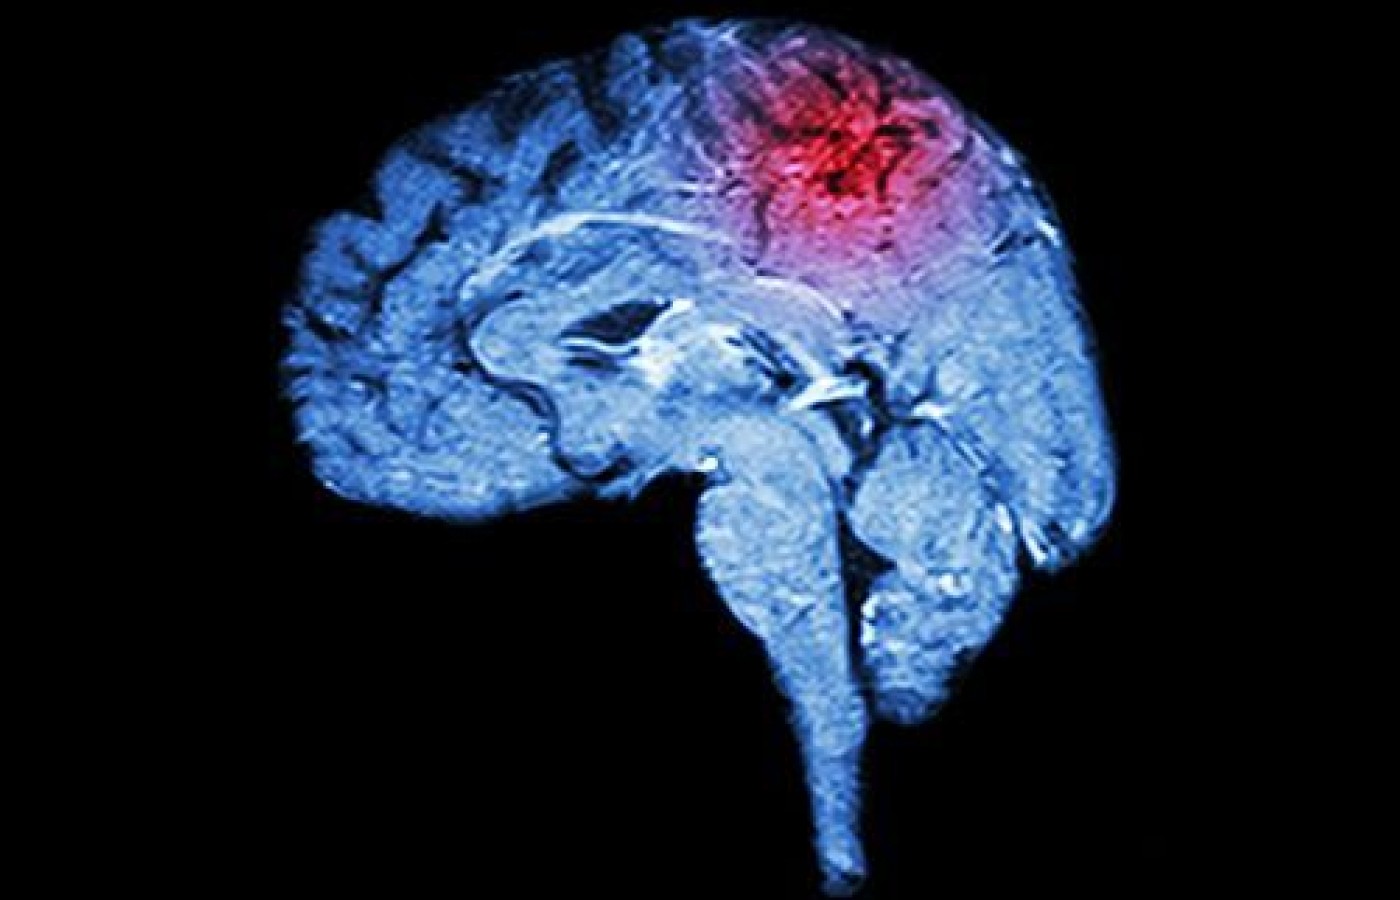

Simple Screening Tests for Stroke and Other Brain Lesions

The drift test, arm rolling and finger rolling are three useful assessments in the identification of upper motor neuron dysfunction. The ability to identify dysfunction of this type is critical to all health care providers in the early diagnosis of patients who may be at elevated risk for an impending stroke or suffering from another brain lesion. Let's review the tests and how to perform them in less than a minute if necessary.

It should be noted that lesions other than strokes can cause the signs listed in the Cincinnati and FAST screenings. Brain lesions causing higher-level motor dysfunction could also be due to injury, tumors, infections, etc. Bell's palsy effecting the seventh cranial nerve causes drooping of the face. (Bell's results in the entire side of the face drooping, while stroke usually causes drooping from the eyebrows down.)

The upper motor lesion causing drift is typically located in the motor cortex of the contralateral side of the affected arm. An exception here is cerebellar lesions, which result in ipsilateral arm drift. In other words, the arm moves away from the side of the lesion for motor lesions of the cortex and toward the side of the lesion for lesions of the cerebellum.